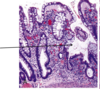

What are the three characteristic symptoms associated with the attached finding of a 40 y/o white male?

Whipple disease - note the distended foamy macrophages in lamina propria that contain T. whippelii.

On inspection you note the distended foamy macrophages in the lamina propria of this image, and you know that this, combined with the patients weight loss, diarrhea and polyarthritis means the patient has?

Which means we are looking at what part of the GI tract that this organism commonly infects?

What stain have you used to deted these T. whippleii?